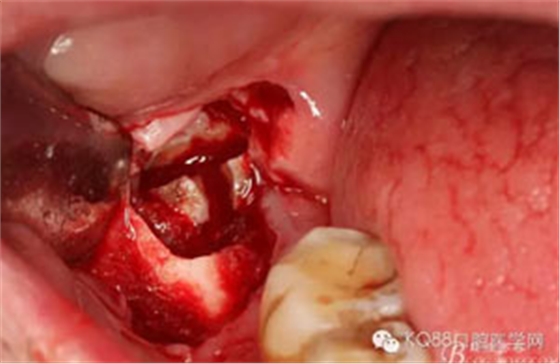

圖6.行角形瓣切開、翻瓣、暴露骨面,可見48牙冠表面有炎性肉芽組織